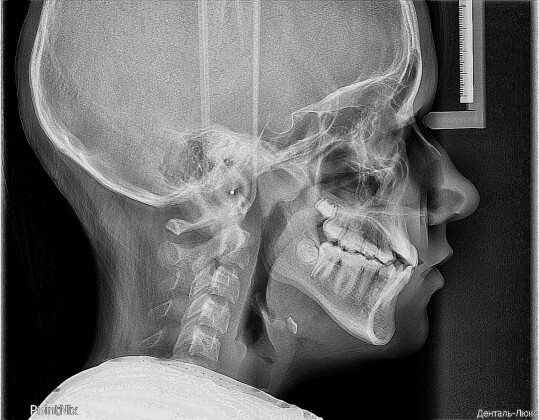

ТЕЛЕРЕНТГЕНОГРАММА (ТРГ)

По данным телерентгенограммы, полученной перед началом лечения, специалист сможет определить положение челюстей относительно друг друга, положение зубов относительно челюстей, тип прикуса, патологии скелета в челюстно-лицевой области, наличие асимметрий.

Анализ телерентгенограммы дает возможность определить направление передвижения зубов, спрогнозировать результат ортодонтического лечения, спланировать проведение челюстно-лицевой операции. Эта методика позволяет предвидеть развитие патологии положения зубных рядов ребенка и, следовательно, заблаговременно принять меры для формирования правильного прикуса.

Телерентгенограмма боковая